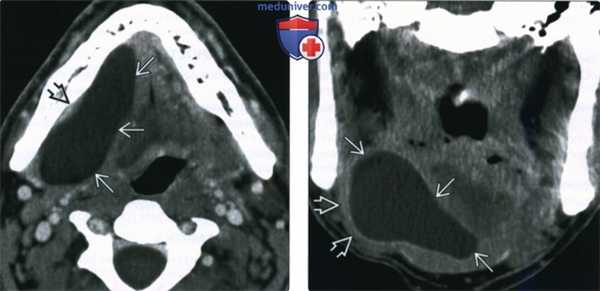

(Слева) КТ с КУ, аксиальная проекция. Крупная простая ранула В, деформирующая правое подъязычное пространство и смещающая челюстно-подъязычную мышцу в латеральную сторону. Утолщения стенок или накопления в них контраста нет, что говорит об отсутствии воспаления.

(Справа) КТ с КУ, коронарная проекция. Челюстно-подъязычная мышца В смещена книзу и латерально крупной, тонкостенной однокамерной кистой В. Простая ранула выглядит идентично эпидермоидной кисте подъязычного пространства. Для постановки диагноза требуется биопсия или четкий анамнез (при врожденной кисте).

(Слева) На аксиальной КТ с КУ определяется большая ПР, растягивающая правую ПЯЖ и приводящая к дугообразному выбуханию челюстно-подъязычной мышцы кнаружи. Заметное контрастное усиление или утолщение стенки кисты отсутствует, как и воспалительные изменения окружающих тканей.

(Справа) На корональной КТ с КУ в отсроченной фазе у этого же пациента определяется дугообразное выбухание челюстно-подъязычной мышцы книзу и кнаружи, обусловленное крупной однокамерной кистой с тонкой стенкой. ПР выглядит идентично эпидермоиду ПЯП, поэтому для установления окончательного диагноза требуется патоморфологическое исследование или точные данные о врожденной природе образования.